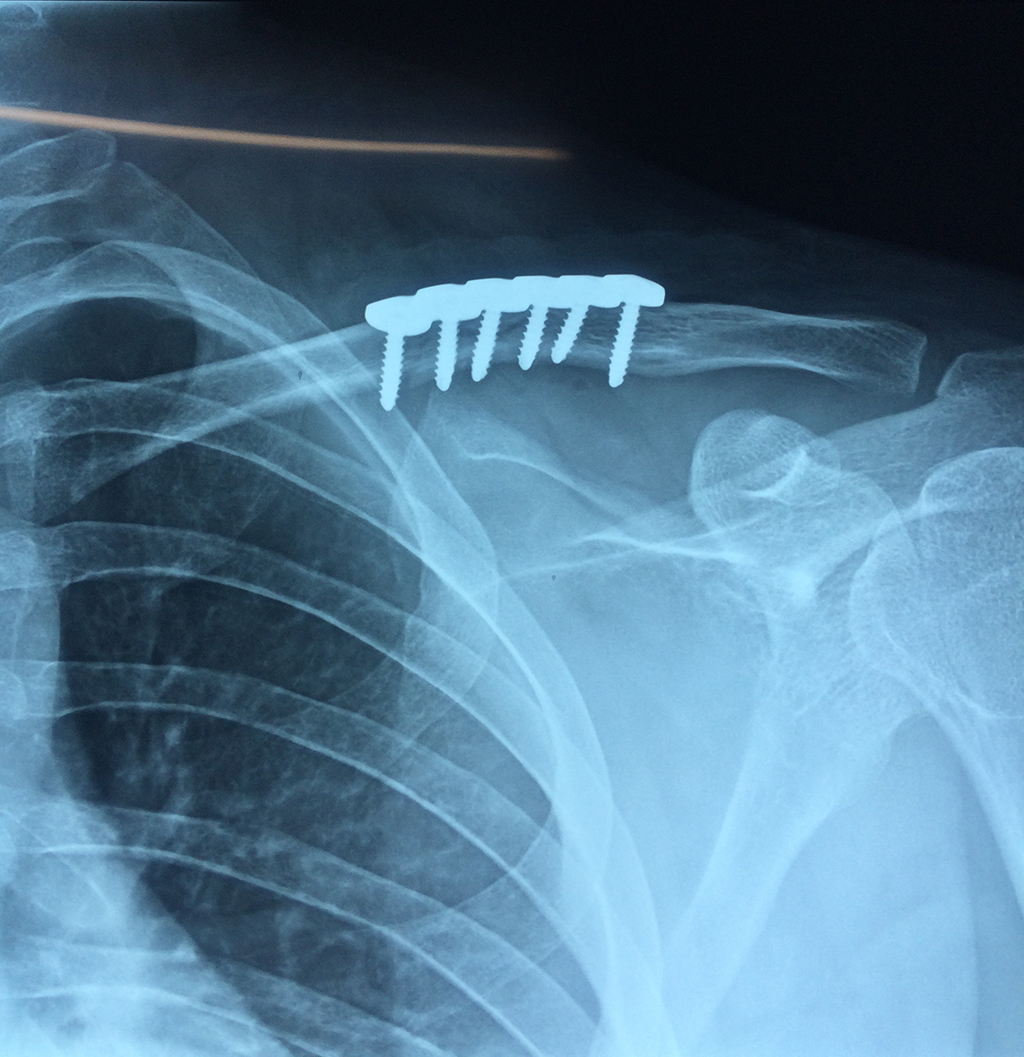

Cirugías de Húmero - Clavícula

La clavícula es un hueso largo, con forma de "S" itálica, situado en la parte anterosuperior del tórax. Junto con la escápula forman la cintura escapular. Se puede palpar por toda su longitud y se extiende del esternón al acromion de la escápula, siguiendo una dirección oblicua lateral y posterior.

Se considera el único medio de unión entre el miembro superior y el tórax. A pesar de su aspecto, similar al de un hueso largo, posee una estructura semejante a la de un hueso plano, ya que carece de epífisis y de diáfisis, lo que la harían entrar dentro de la clasificación de hueso largo. Carece de un canal medular propiamente dicho.